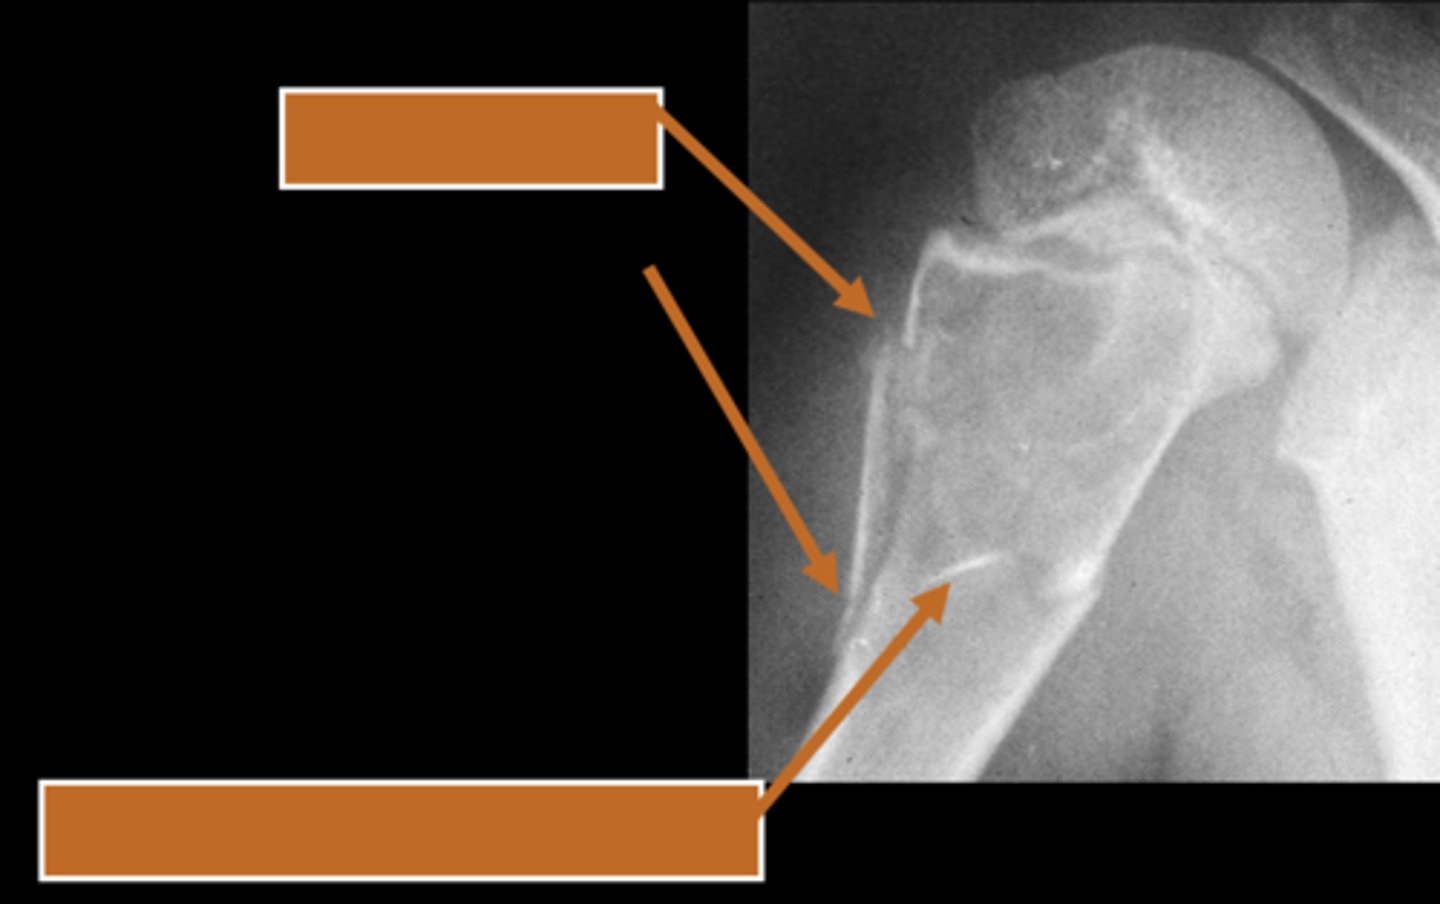

Geographic bone blister

ID radiographic feature of non-ossifying fibroma indicated by top arrow

Septations

ID radiographic feature of non-ossifying fibroma indicated by bottom arrow